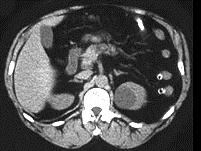

问题 1986年Bosniak根据CT征象提出肾囊性病变四级分类法,下列图片中的肾囊肿属于哪一类 ( )

选项 A、BosniakⅣ类 B、以上都不是 C、BosniakⅡ类 D、BosniakⅢ类 E、BosniakⅠ类

答案 E